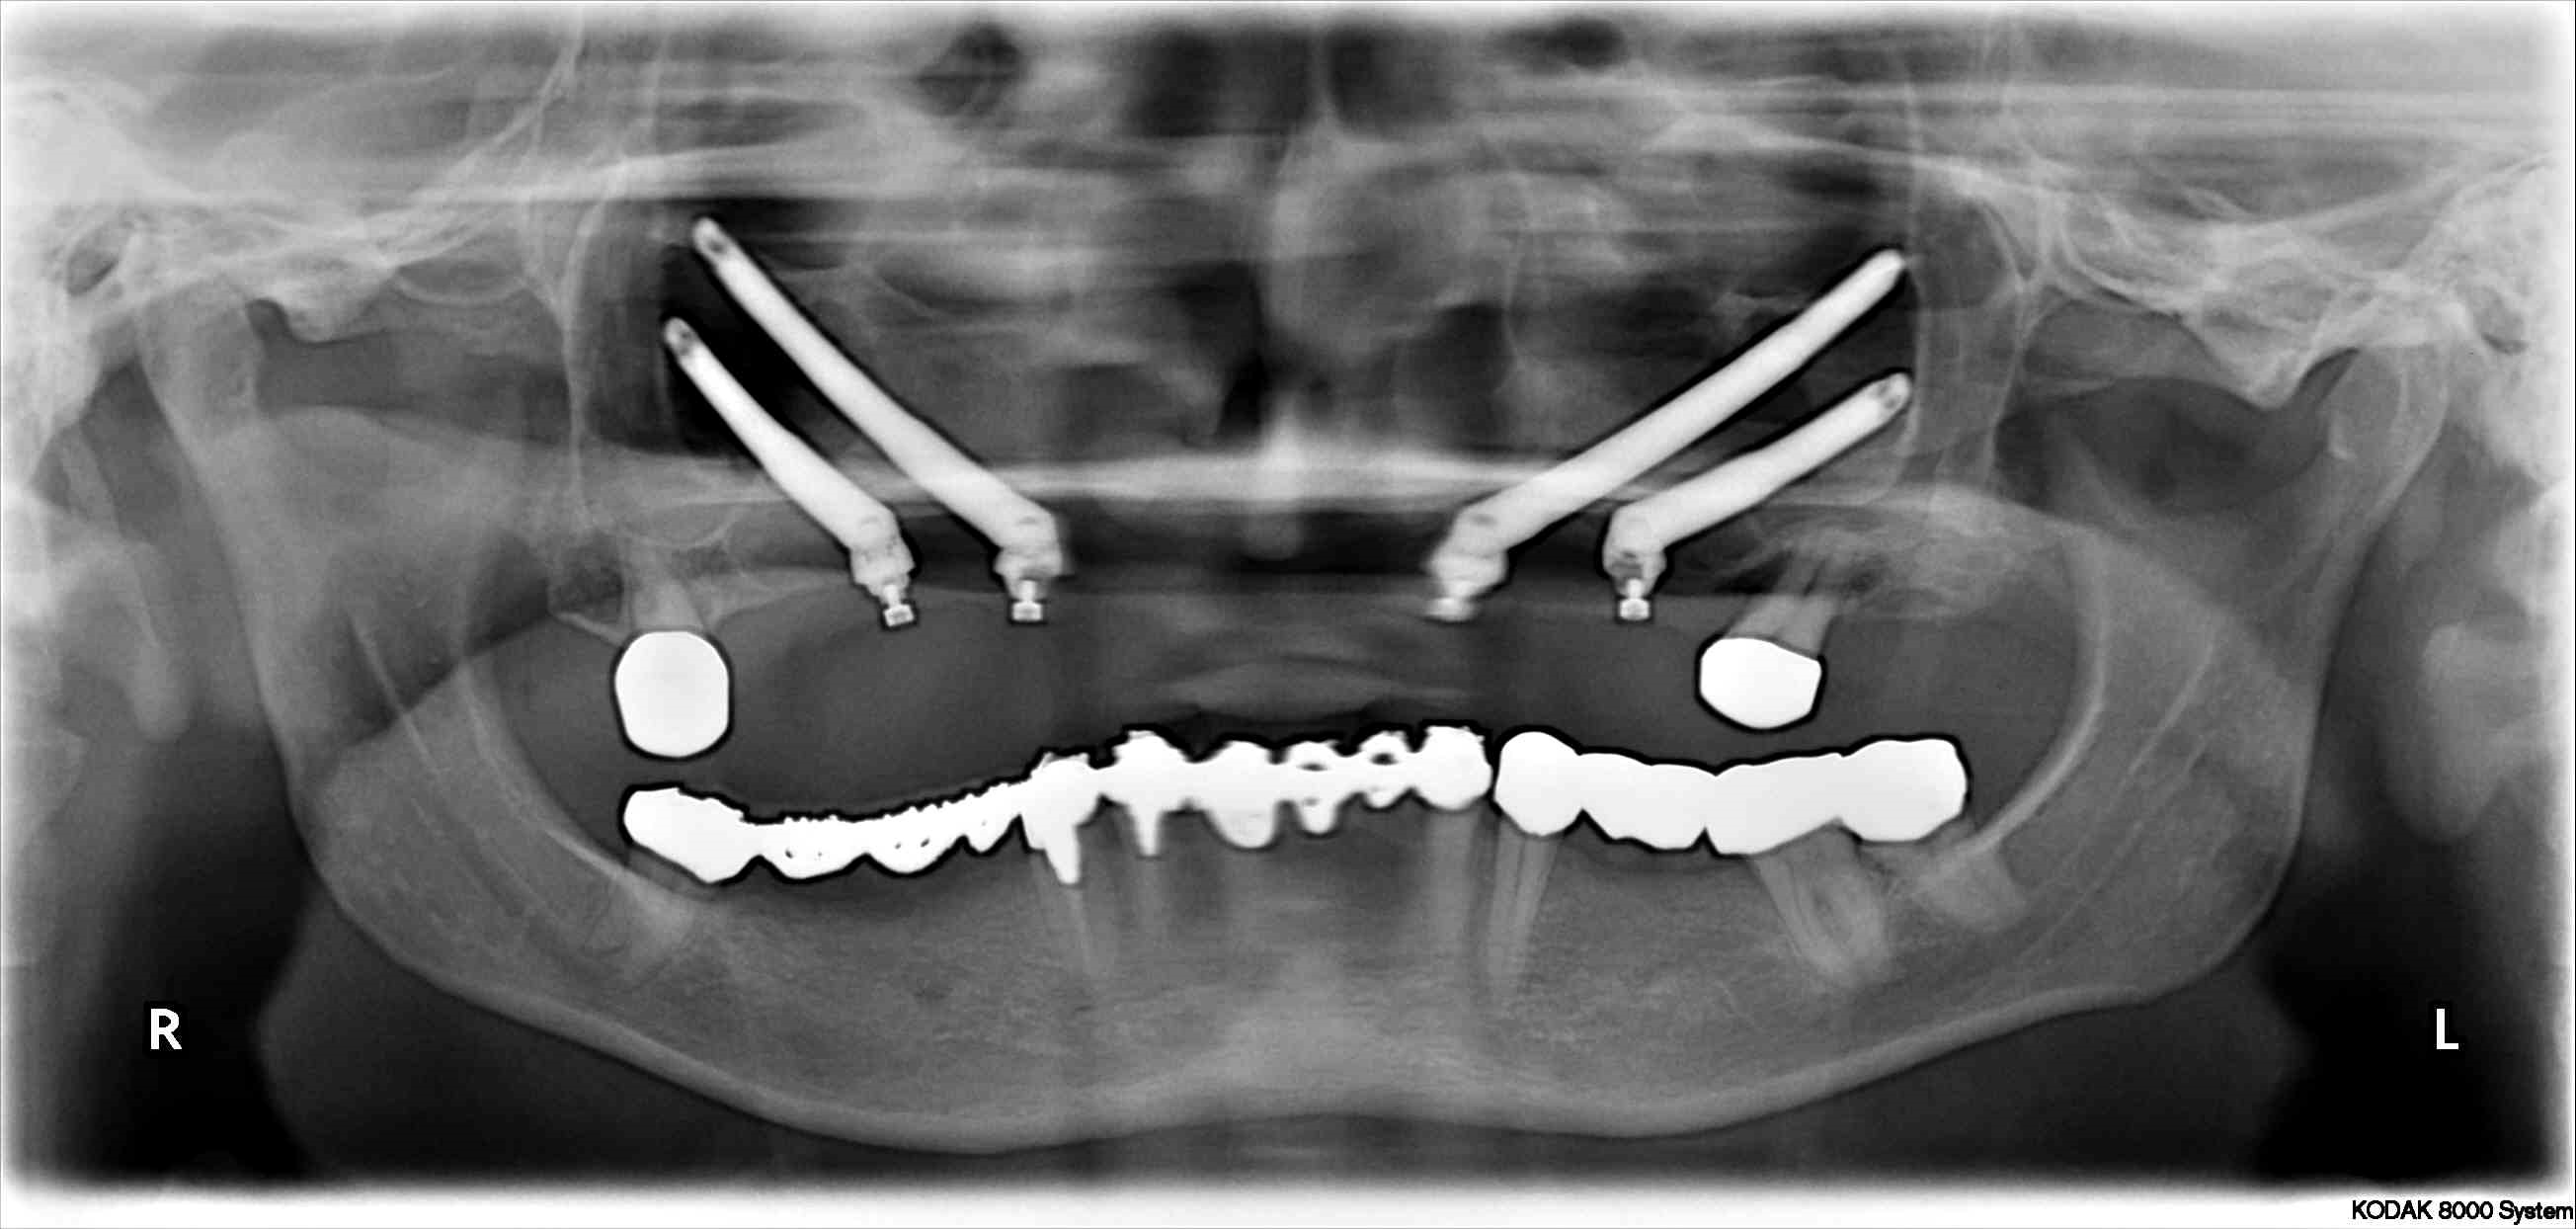

Lična (zigomatična) kost je kost na obrazu, ki tvori spodnji in lateralni rob orbite ter zgornjo in lateralno steno maksilarnega sinusa. Telo lične kosti je praviloma dovolj veliko, da se vanj zasidra 10 do 14 mm zigomatičnega vsadka s premerom 4 mm, prav tako pa je dovolj trdna za dobro primarno stabilnost vsadka in njegovo takojšnjo obremenitev. Kadar v zadnjih segmentih čeljusti ni dovolj kosti in vsadkov ni mogoče vgraditi, jih pa je mogoče vgraditi v sprednji segment, se zasnova All on 4 izvede na dveh zigomatičnih (po en na vsaki strani) in dveh klasičnih zobnih vsadkih. Pri najtežjih primerih atrofije, kjer v zgornji čeljusti sploh ni kosti, se namestita po dva zigomatična vsadka na vsaki strani, kar pomeni, da celotno konstrukcijo All on 4 podpirajo samo zigomatični vsadki (zasnova, znana pod nazivom quad zygoma).

Kirurški postopek vgradnje vsadkov se izvaja samo s splošno anestezijo. Je nekoliko bolj zapleten od namestitve zobnih vsadkov ter zahteva več kirurškega znanja in veščin ter dobro poznavanje anatomije srednje in zgornje tretjine obraza. Kljub temu je uspešnost teh vsadkov zelo dobra oziroma enako dobra kot pri klasičnih zobnih vsadkih. Bolniki praviloma hitro okrevajo, brez večjih po operacijskih težav.